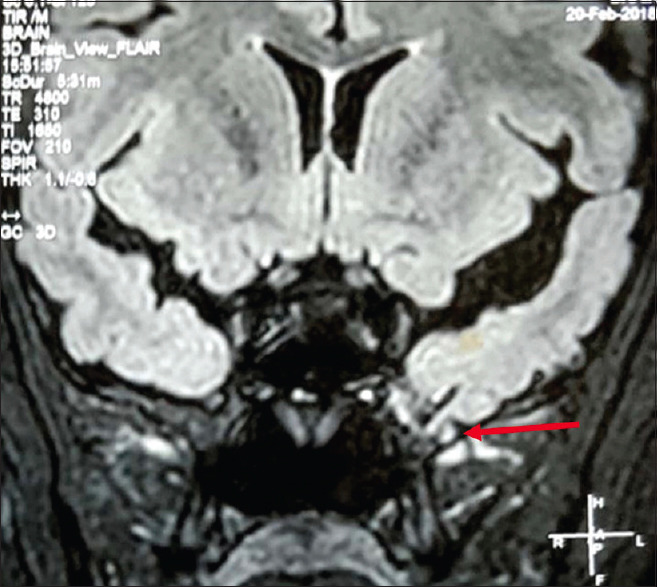

Abstract: In the present study patients with previously diagnosed MRI-negative temporal lobe epilepsy (TLE) on long-term video electroencephalography (VEEG) monitoring were re-evaluated with high resolution 3T MRI brain to look out for a skull base temporal lobe encephalocoele (TE). A total of 234 VEEGs were analyzed. TLE had been diagnosed in 104 patients based on semiology, ictal, interictal EEG data, and brain positron emission tomography (PET) studies. Of these, 99 patients had temporal lobe abnormality (78 had mesial temporal sclerosis, 8 had tumor, 3 had focal cortical dysplasia, and 10 had mixed pathology). Out of the five 1.5T MRI-negative TLE patients, two patients were diagnosed with TE on subsequent 3T MRI brain scans and one patient underwent electrocorticography-guided tailored resection for complete removal of epileptogenic tissue; with Engels class I seizure freedom at one year follow-up. We propose that TE should be carefully searched for, as a cause of refractory TLE, using high-resolution MRI sequences.